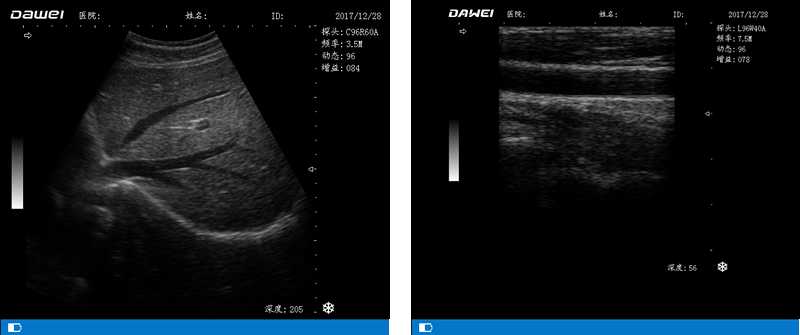

高陣元 高清晰度 多功能

多倍率顯示 病變診斷更準確